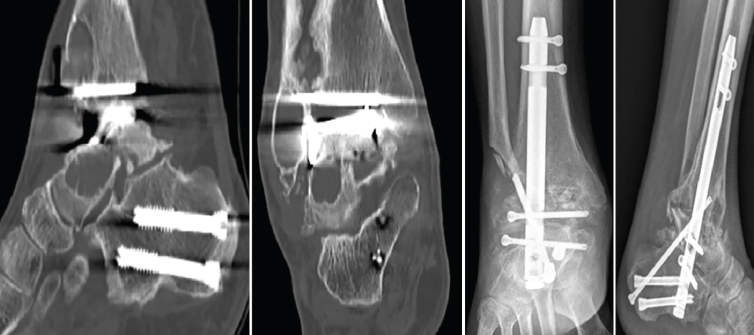

Figura 3. Imágenes del clavo tibiotalocalcáneo roto a través de la trinchera ósea y maniobra de extracción con guías endomedulares ayudadas por la impactación directa en la muesca realizada en el clavo.

Se reintervino al paciente realizando la extracción del fragmento distal del clavo con el sistema extractor del mismo. Para la extracción del extremo proximal fue necesario, además de la utilización de las guías curvadas, abordar el foco de la pseudoartrosis hasta visualizar el clavo y, con una fresa de alta velocidad, hacer una muesca en el mismo. Mediante la percusión sobre un escoplo apoyado en la muesca realizada en el clavo y con la ayuda de las agujas guía introducidas a través del clavo, se consiguió la extracción del extremo proximal a través de la planta del pie (Figura 3). Se legró la superficie articular tibiotalar y se colocó injerto de cresta ilíaca, fijando la artrodesis con una placa TTC (Palex Medical), aunque la articulación subtalar estuviese artrodesada, para dar mayor solidez al montaje.

Figura 4. Imágenes de tomografía computarizada con lisis alrededor de la prótesis con deformidad en varo. Se aprecia la osteosíntesis para la osteotomía del calcáneo realizada previamente. Imágenes radiográficas tras la artrodesis tibiotalocalcánea con clavo retrogrado con tornillo tibiotalocalcáneo del calcáneo a la tibia oblicuo.

Se realizó, por vía transperoneal, la extracción de la prótesis de tobillo y una ATTC con clavo Phoenix® (Zimmer Biomet) de 11 mm de diámetro y 180 mm de longitud, reforzando el montaje con un tornillo oblicuo desde el calcáneo a la tibia, como en el caso número 2. El peroné extraído por el abordaje lateral se utilizó como injerto autólogo corticoesponjoso (Figura 4).

Figura 5. Imágenes de tomografía computarizada con el clavo roto. Finalización de la extracción con la guía curvada a través de la luz del clavo. Rescate con placa tibiotalocalcánea e injerto corticoesponjoso colocado en el foco.

Se reintervino al paciente realizando la extracción del fragmento distal del clavo sin dificultad. Para la extracción del fragmento proximal, se practicó, como en el caso anterior, además de la utilización de las guías curvadas, en el foco de pseudoartrosis, una muesca en el clavo con la fresa de alta velocidad para apoyar el escoplo. De ese modo, con la ayuda de la percusión directa sobre el clavo, se consiguió la extracción del extremo proximal a través de la planta del pie. Tras legrar las superficies articulares y aportar injerto tricortical de cresta ilíaca, se realizó la fijación con una placa de artrodesis TTC (Palex Medical) (Figura 5).